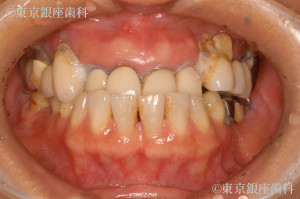

ボロボロの歯の症例

患者様プロフィール

40代 男性

疾患 歯周病

施術内容 ワンデイインプラント

治療期間 9か月 費用 375万円(税込)

Before

治療概要 概要:虫歯、歯周病、治療:上ワンデイインプラント、下総入れ歯